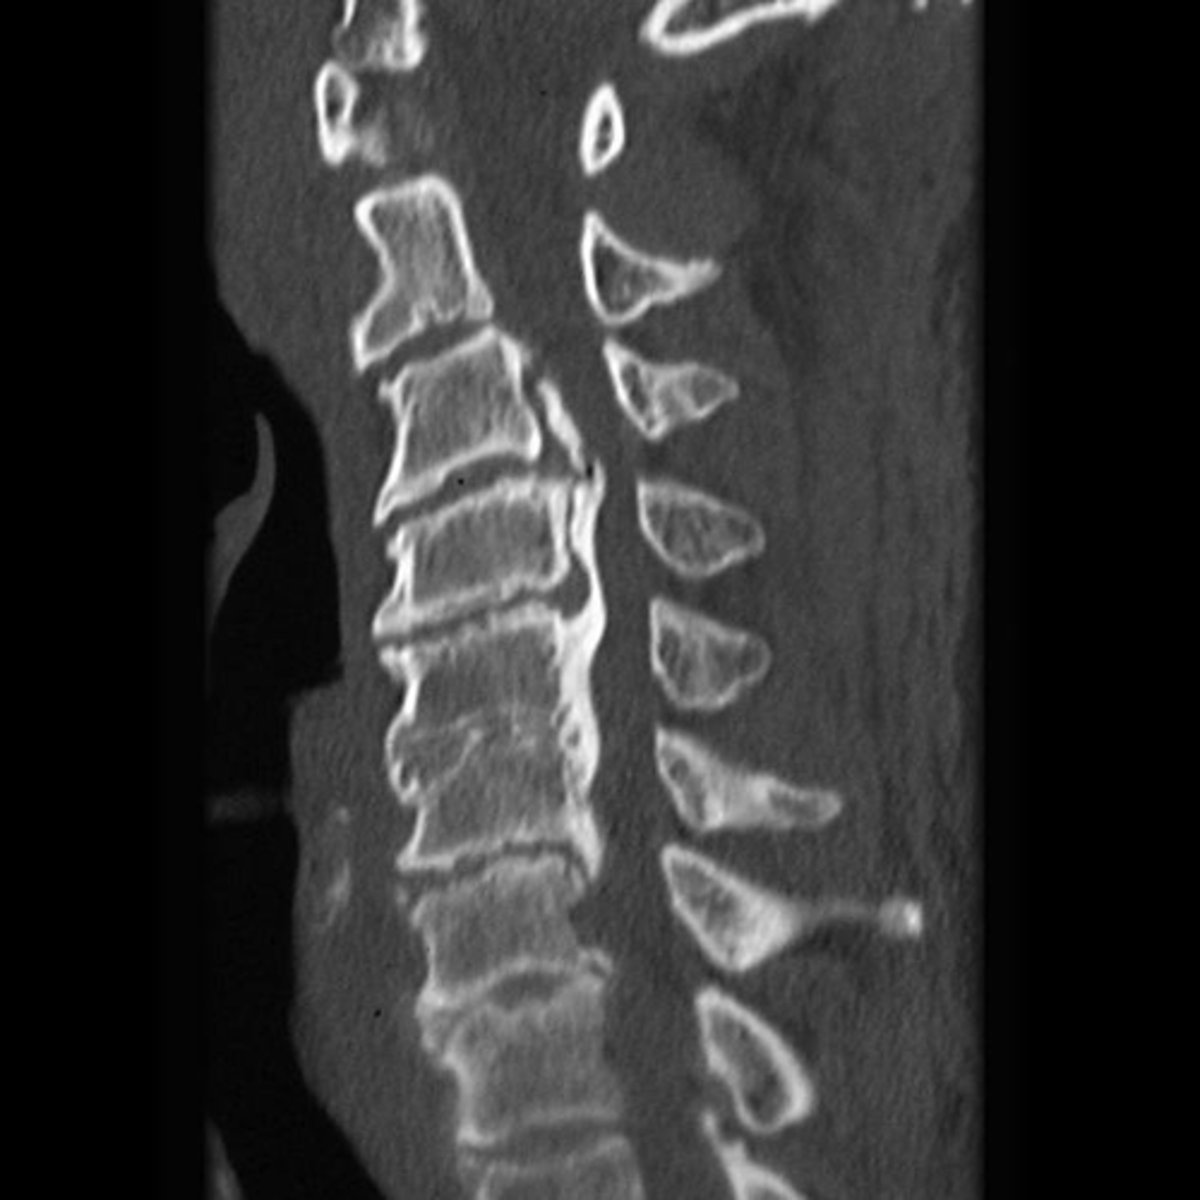

- Calcification of anterior longitudinal ligament

- Intercalary bone

- Preserved disc height across 4 levels

List at least 3 findings

Ossification of the posterior longitudinal ligament (OPLL)

What complication has occurred in the cervical spine?

Diffuse idiopathic skeletal hyperostosis (DISH)

Most likely diagnosis?

Neurosurgeon referral

Next step?

No

Would you adjust this patient?

What is the main finding on the CT study?

Would you adjust this patient's cervical spine?